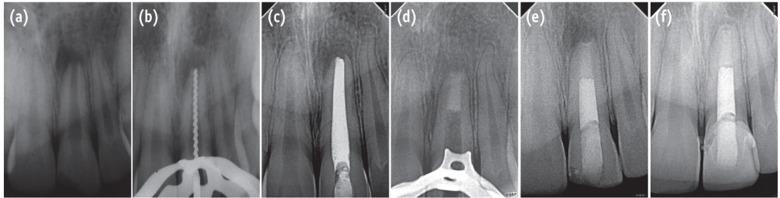

Use of an apical plug in management of cases with open apices has gained popularity in recent years. Biodentine, a new calcium silicate-based material has recently been introduced as a dentine substitute, whenever original dentine is damaged. This case report describes single visit apexification in a maxillary central incisor with necrotic pulp and open apex using Biodentine as an apical barrier, and a synthetic collagen material as an internal matrix. Following canal cleaning and shaping, calcium hydroxide was placed as an intracanal medicament for 1 mon. This was followed by placement of small piece of absorbable collagen membrane beyond the root apex to serve as matrix. An apical plug of Biodentine of 5 mm thickness was placed against the matrix using pre-fitted hand pluggers. The remainder of canal was back-filled with thermoplasticized gutta-percha and access cavity was restored with composite resin followed by all-ceramic crown. One year follow-up revealed restored aesthetics and function, absence of clinical signs and symptoms, resolution of periapical rarefaction, and a thin layer of calcific tissue formed apical to the Biodentine barrier. The positive clinical outcome in this case is encouraging for the use of Biodentine as an apical plug in single visit apexification procedures.

近年来,使用根尖屏障治疗根尖孔开放的病例越来越普遍。Biodentine是一种新型的硅酸钙基材料,最近被引入作为牙本质替代物,用于原始牙本质受损的情况。本病例报告描述了使用Biodentine作为根尖屏障、合成胶原材料作为内部基质,对上颌中切牙牙髓坏死且根尖孔开放进行一次性根尖诱导成形术。根管清理和预备后,放置氢氧化钙作为根管内药物1个月。随后在根尖外放置一小片可吸收胶原膜作为基质。使用预成型手动充填器将5毫米厚的Biodentine根尖屏障放置在基质上。根管其余部分用热塑牙胶回填,用复合树脂修复髓腔,然后制作全瓷冠。一年的随访显示美学和功能恢复,无临床症状和体征,根尖周稀疏区消失,Biodentine屏障根尖处形成一层薄的钙化组织。该病例的积极临床结果鼓励在一次性根尖诱导成形术中使用Biodentine作为根尖屏障。